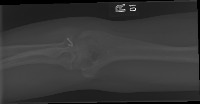

trish abnormal/normal Computer Vision Project

Medical Diagnostics: The model can be used in hospitals, clinics, or doctor practices to help provide a quick preliminary diagnosis for patients, especially in urgent care settings. Identifying fractures and hairline fractures can expedite treatment and intervention plans.

Telemedicine App: The model can be integrated into telemedicine applications to provide virtual first-line diagnostics for patients who cannot readily access medical facilities. This is particularly useful in remote areas and for elderly or disabled people.

Emergency Rescue: The model can be used by rescue teams in disaster-stricken areas to quickly identify serious injuries that need immediate attention, allowing for more informed decision-making and prioritization of patients.

Training Medical Students: This model can be used to educate medical students in the process of identifying fractures and hairline fractures, providing valuable, hands-on training experience without the risks associated with real-world diagnostics.

Manufacturing and Industrial Safety: If similar models are developed for other types of X-rays, they can be used in situations involving workplace injuries in heavy industries. Quick diagnosis can help provide immediate necessary treatment and document the extent of injuries for workers' compensation claims.